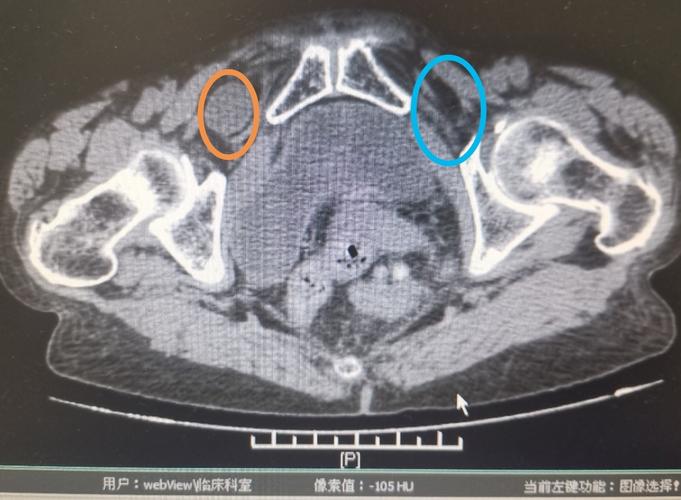

闭孔疝CT

闭孔疝ct图片

闭孔疝ct表现图